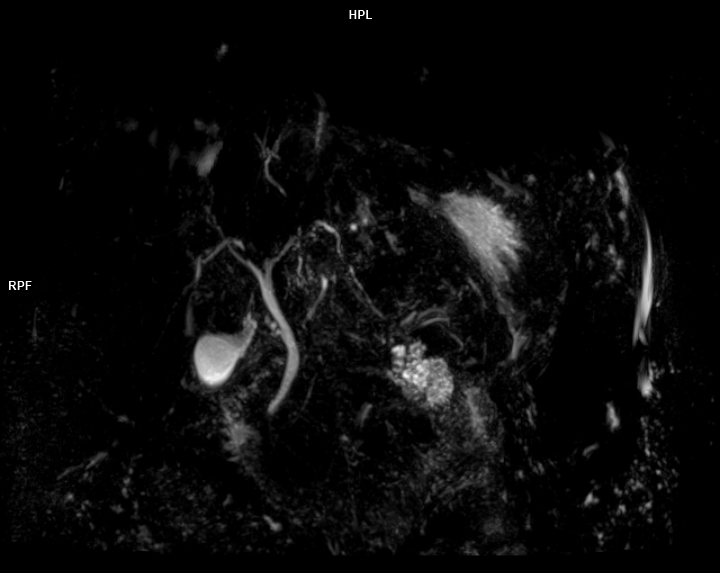

• 3 TESLA MR ÇEKİM GÖRÜNTÜLERİ

3 Tesla MR Çekim Görüntüleri

• 3 Tesla MR Çekim Görüntüleri